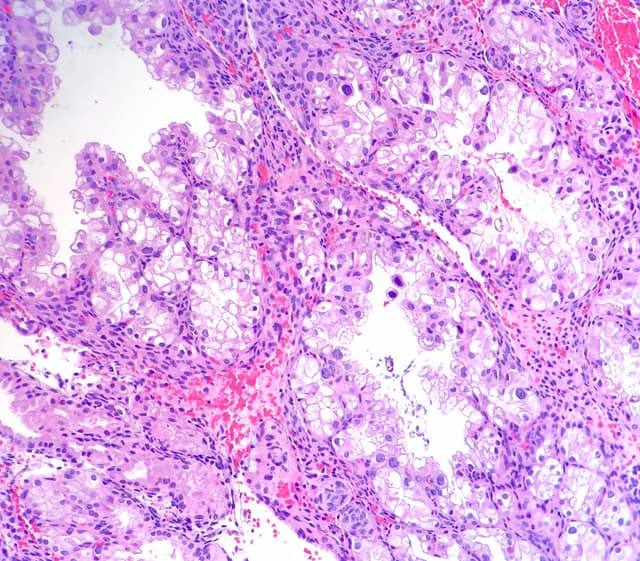

Colorectal cancer

Polyp with cancer